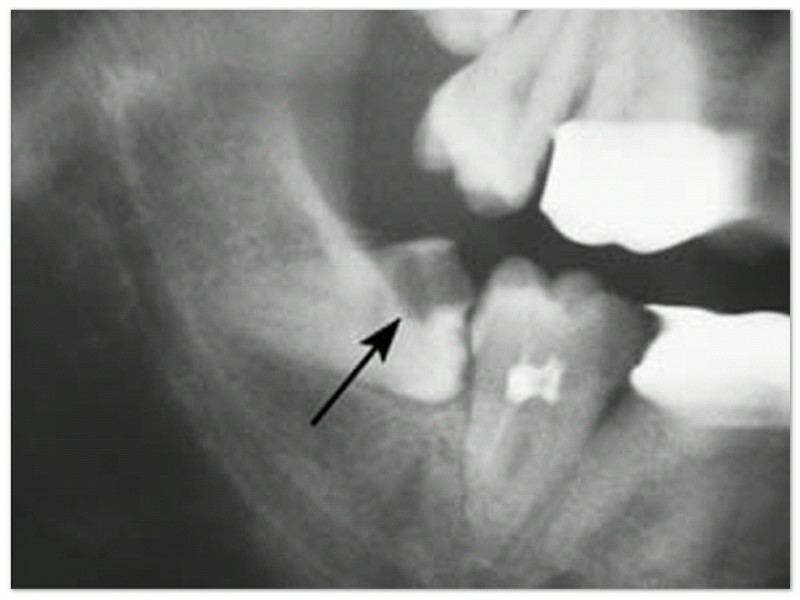

Yang pertama tentu saja dengan cara rutin kontrol ke dokter gigi. Di sekitar umur 12-15 tahun, mahkota gigi bungsu sudah terbentuk sempurna sehingga dapat terlihat apabila dilakukan foto radiograf. Dari foto radiograf tersebut, dokter gigi bisa memprediksi dapat atau tidaknya gigi bungsu tersebut tumbuh dengan maksimal.

Apabila kemungkinan besar gigi tersebut akan menimbulkan masalah, dapat dilakukan tindakan pencabutan pencegahan (pada usia kurang dari 20 tahun). Pencabutan pencegahan ini lebih menguntungkan karena akar gigi sulung masih pendek, tulang lebih lunak, sehingga penyembuhan pun akan lebih cepat.